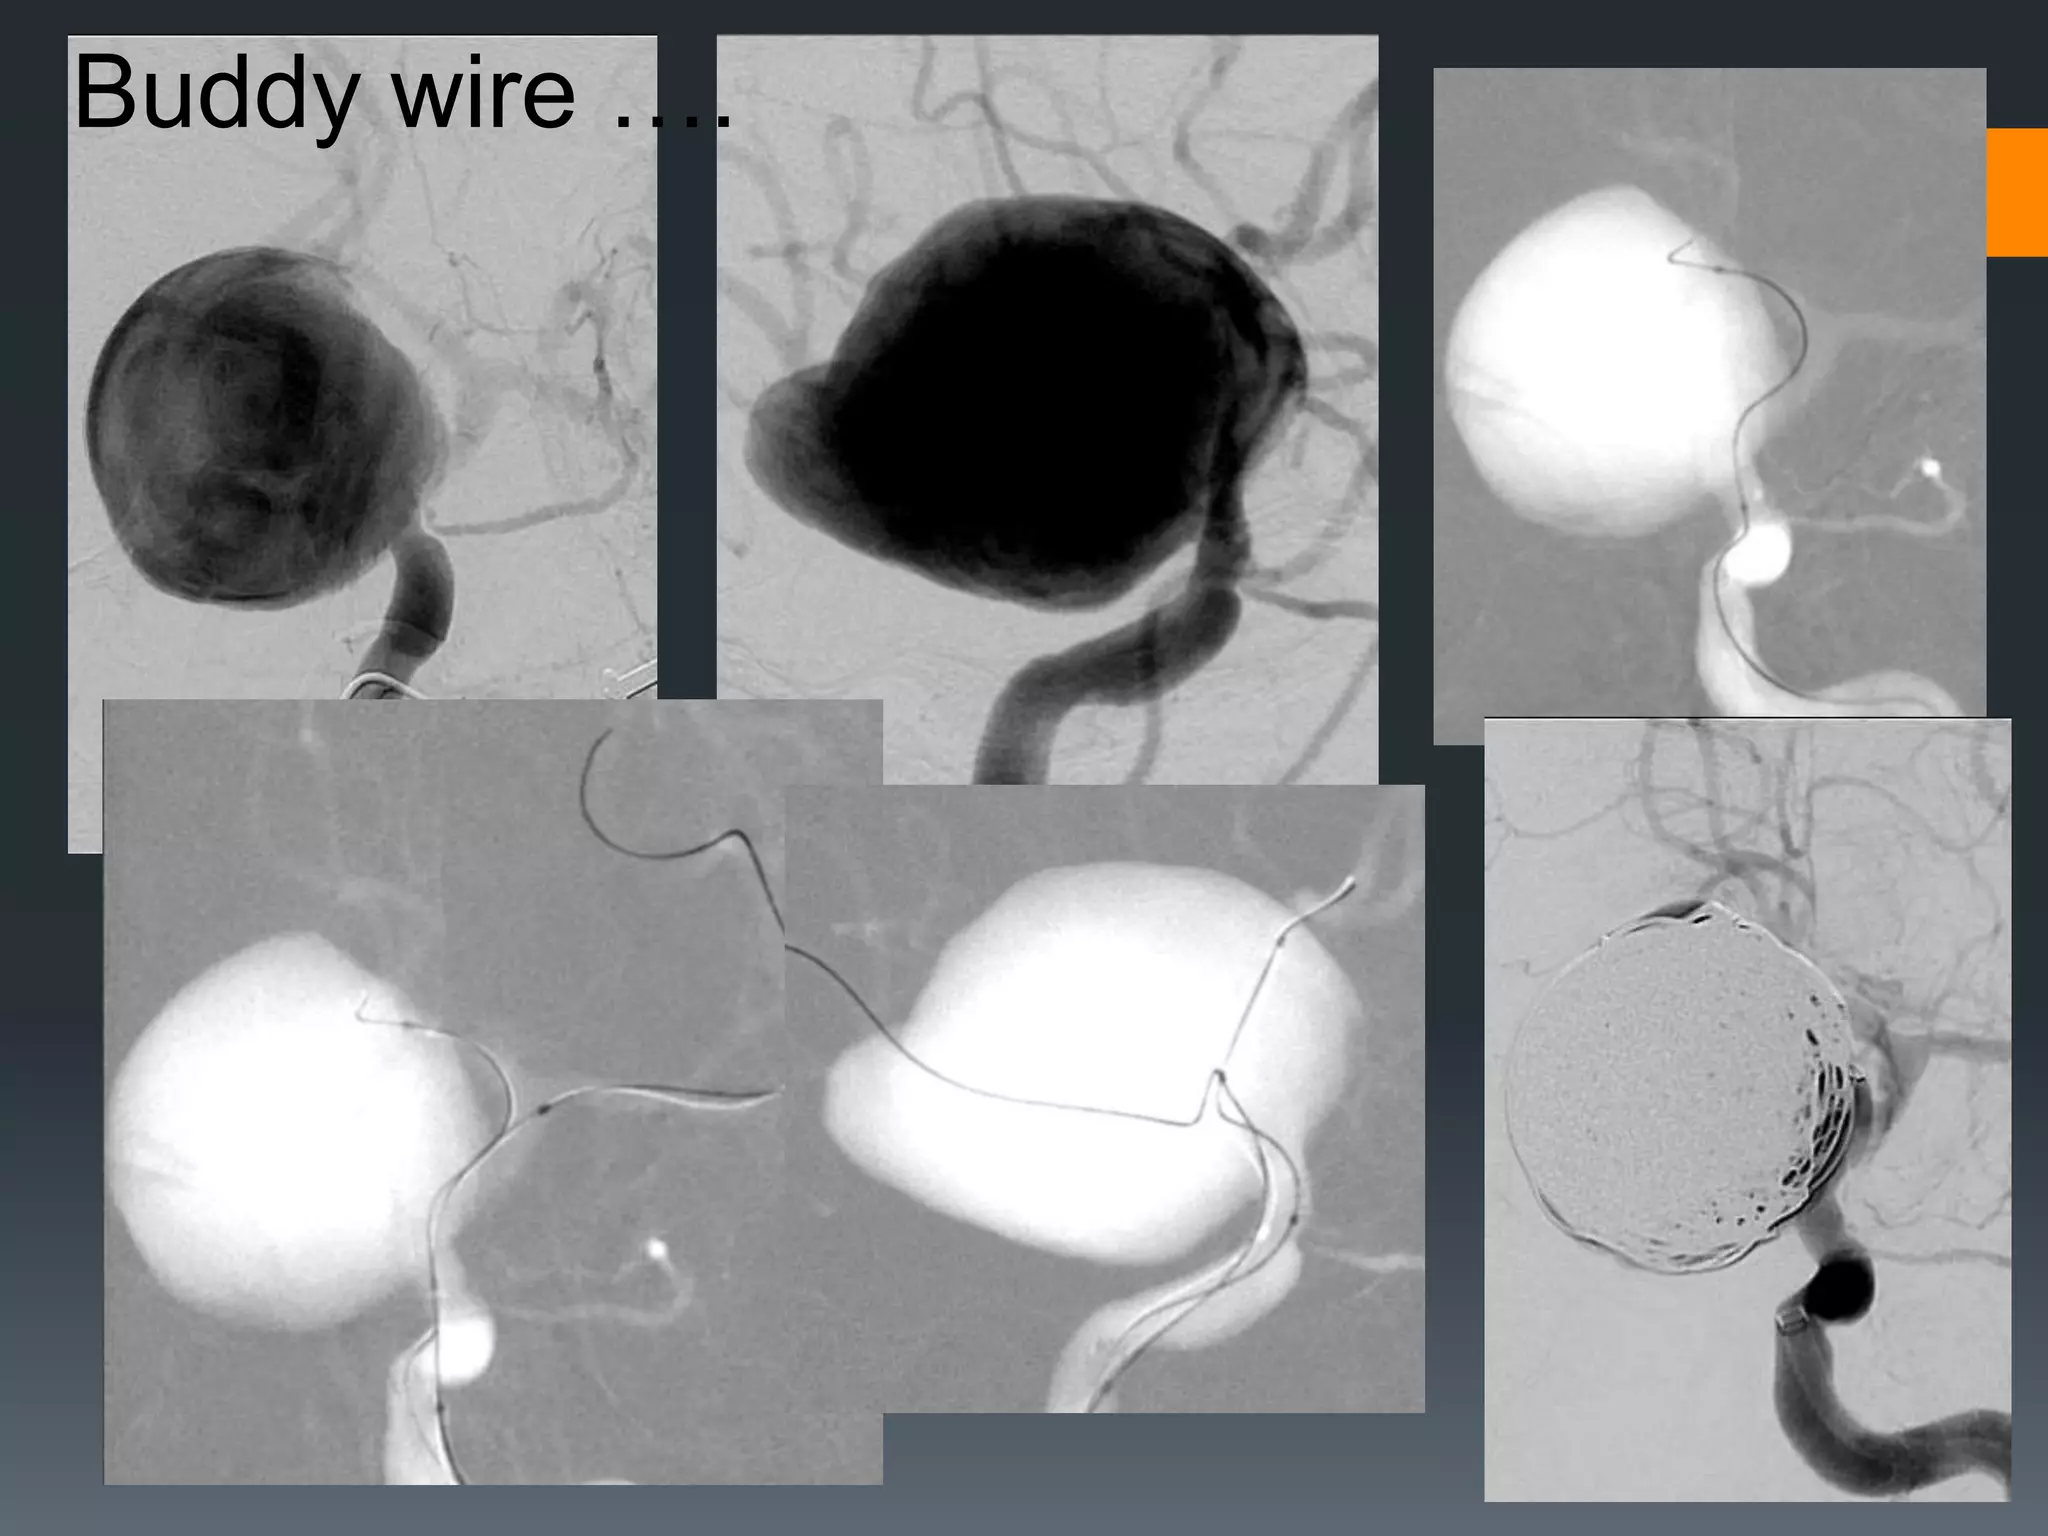

This document discusses tricks and techniques for difficult cannulations during neurointerventional procedures. It outlines strategies for accessing the aortic arch, internal carotid artery (ICA), and areas distal to aneurysms. Long sheaths, distal access catheters, and co-axial techniques are presented as options that have improved cannulation success. Guidance on sheath and catheter selection is provided for different vessel paths. The importance of catheter placement as high as possible in the ICA is emphasized. Reverse curve cannulations are also mentioned. Overall, the document stresses that careful cannulation is critical for procedural success and different strategies may be needed depending on the vessel target.